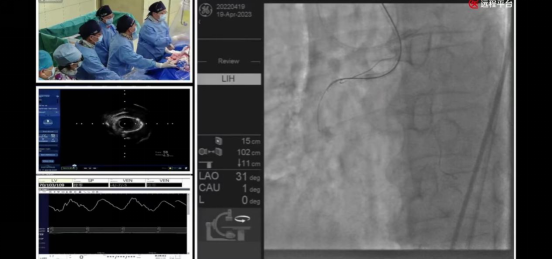

在19日上午8时进行的全球手术实况直播首秀中,哈尔滨医科大学附属第一医院心血管内科李悦教授带领的心血管内科团队为全球医生与医学爱好者献上两场精彩的手术演示:

哈尔滨医科大学附属第一医院心血管内科介入团队—井玲教授、涂应锋教授、盛力教授、董国教授、曹阳副教授、石治宇副教授、王定宇主治医生,首先展示了在冠状动脉CTA三维重建技术(原创性技术)指导下,应用逆向技术成功开通右冠状动脉慢性完全闭塞病变,并通过双球囊-导丝交错切割技术(原创性技术)有效处理球囊不能通过的病变,顺利置入2枚支架。

哈尔滨医科大学附属第一医院心血管内科介入团队—公永太教授、赵继义教授、李俭强副教授、孙党辉副教授、张松副教授、王定宇主治医生,展示了基于冠状动脉CTA三维重建技术(原创性技术)制定的术前手术策略。术中,公永太教授根据术前策略,应用OCT指导冲击波球囊处理前降支重度钙化病变并成功保护闭塞高危对角支,顺利置入2枚支架。